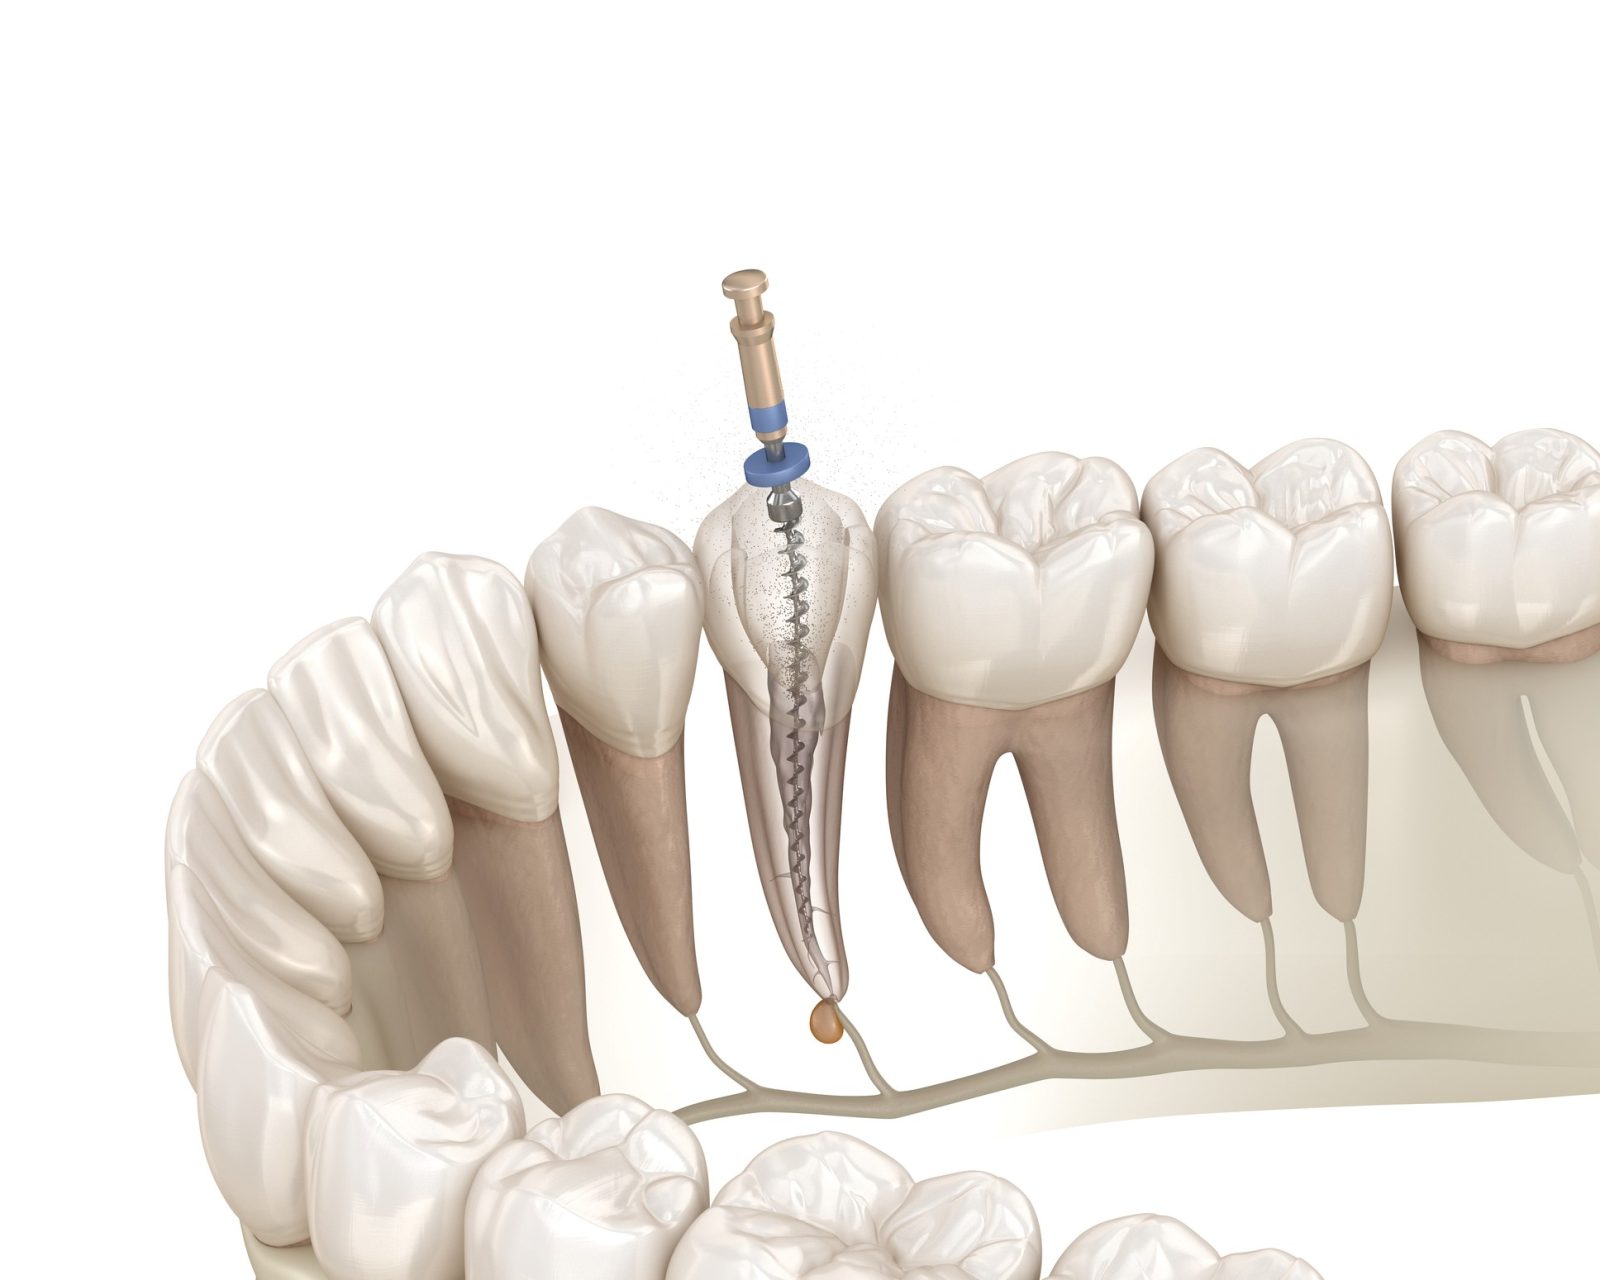

感染部位を除去する「ニッケルチタンファイル」

根管治療では、感染した神経や細菌を取り除くために、「ファイル」と呼ばれる細いヤスリ状の器具を使用します。多くの歯科医院では一般的にステンレス製のファイルが使われています。ステンレスは硬くしなりにくいため、曲がりくねった根管の形に合わせて動かすのが難しいという欠点があります。無理に操作すると、根の壁に傷をつけたり、最悪の場合は根に穴を開けてしまうリスクもあります。

当院では、このリスクを避けるために、高い柔軟性と弾力性を持つ「ニッケルチタン製ファイル」を使用しています。ニッケルチタンはしなやかに曲がる性質があり、どんなに複雑な根管形状にもスムーズに追従できるのが特徴です。この柔軟性によって、根の内部を傷つけることなく、感染部位だけを効率的かつ安全に除去することが可能になります。